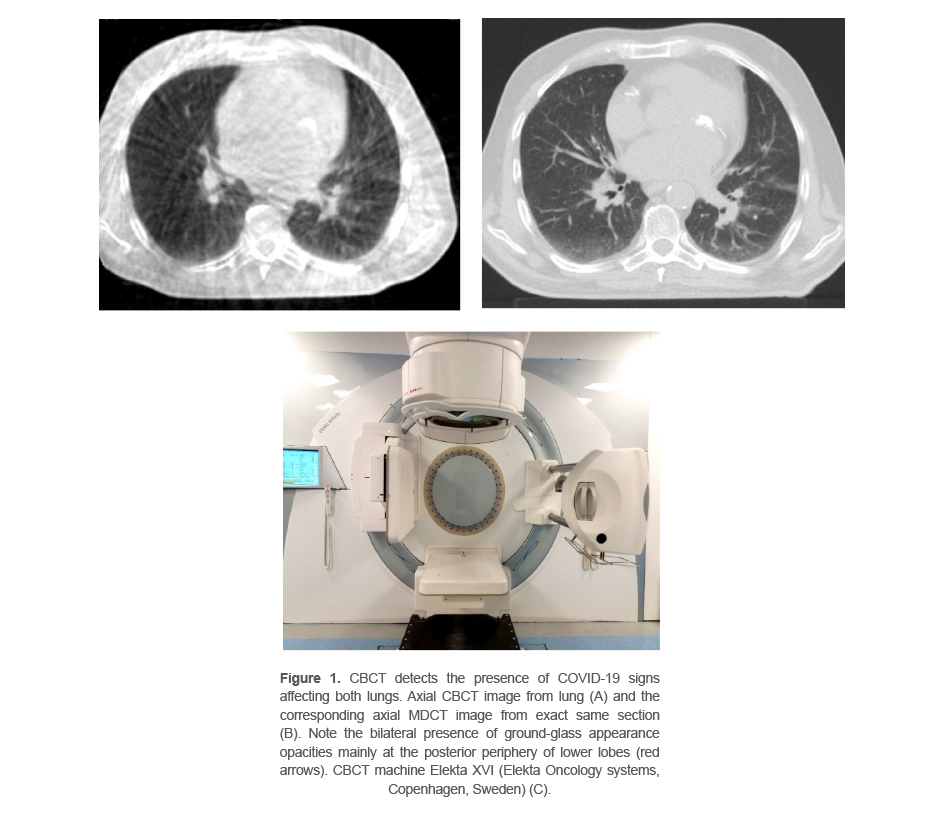

We reported the case of a 30-year-old woman with diagnosed diffused lung B-cell lymphoma cancer referred for adjuvant radiotherapy after chemotherapy to Erfan radiation oncology center, Tehran, Iran. Her non-contrast computed tomography scan for simulation was done after consultation on August 23, 2021. The patient underwent the radiotherapy for 3 weeks using intensity-modulated radiotherapy technique. Treatment was started on August 29. The IGRT protocol used was on-line daily CBCT (CBCT scans were acquired with Elekta XVI (Elekta Oncology systems, Copenhagen, Sweden), version 5.03.). The imaging protocol used for chest CBCT is medium Field of View (FOV) (projected field width and length at isocenter are 27.6727.67 cm2 with 120 kVp). Signs of SARS-CoV-2 findings were observed in her CBCT images on the start of her third week radiotherapy treatment and was referred for consultation and further evaluation. The nasopharyngeal PCR Coronavirus SARS-COV-2 test was positive and her symptoms started in 3 days. The radiotherapy treatment was postponed for 3 weeks and started after her second COVID -19 test became negative. The acquired CBCT is shown in figure 1. Symptoms due to the SARS-CoV-2 were detectable in her images.

Figure 1. CBCT detects the presence of COVID-19 signs affecting both lungs. Axial CBCT image from lung (A) and the corresponding axial MDCT image from exact same section (B). Note the bilateral presence of ground-glass appearance opacities mainly at the posterior periphery of lower lobes (red arrows). CBCT machine Elekta XVI (Elekta Oncology systems, Copenhagen, Sweden) (C).